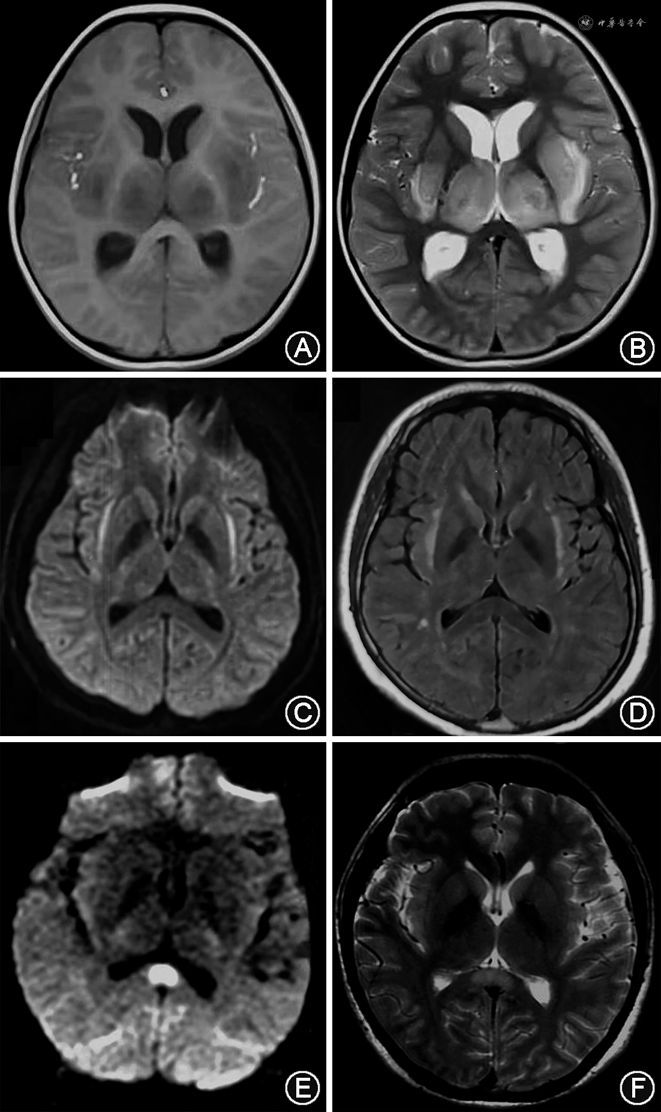

5.副感染性脑病(para-infectious encephalopathy):继发于系统性感染性疾病(CNS之外的感染性疾病)的一组急性脑病综合征,包括急性坏死性脑病(acute necrotizing encephalopathy)、伴胼胝体压部可逆性病变的轻度脑病综合征(mild encephalopathy with a reversible splenial lesion syndrome)、伴(或不伴)屏状核病变的发热感染相关癫痫综合征(febrile infection-related epilepsy syndrome)等(图2)。这是一组机制有待阐明的感染相关脑病综合征。副感染性脑病不是由病毒直接侵袭CNS引起,也不属于适应性免疫介导的特异性自身免疫反应,而可能与细胞因子风暴导致的炎性综合征和个体遗传因素等相关,例如COVID-19相关的急性坏死性脑病[26],偶可见于疫苗接种后。以往有所谓的“感染后脑炎”的提法,可能部分涵盖到副感染性脑病;而由感染诱发的抗神经抗体阳性脑炎,目前已归类为AE。